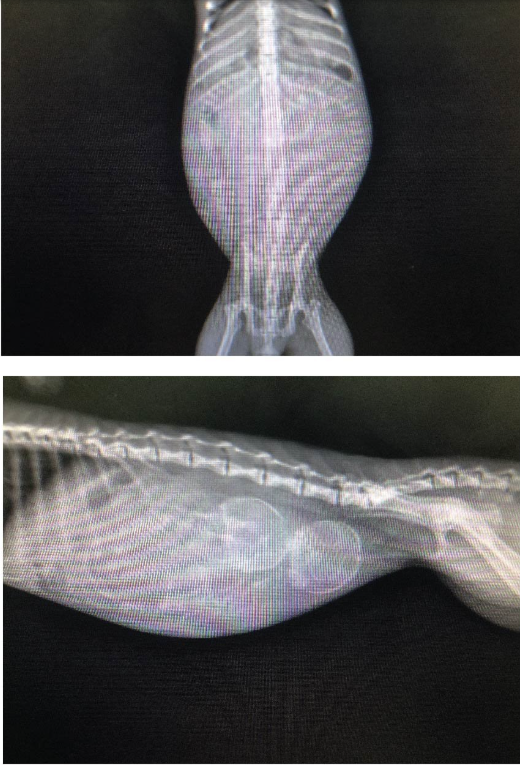

X-rays (Radiography): To determine the number, size, and orientation of the fetuses, and to check if the pelvic canal is wide enough.